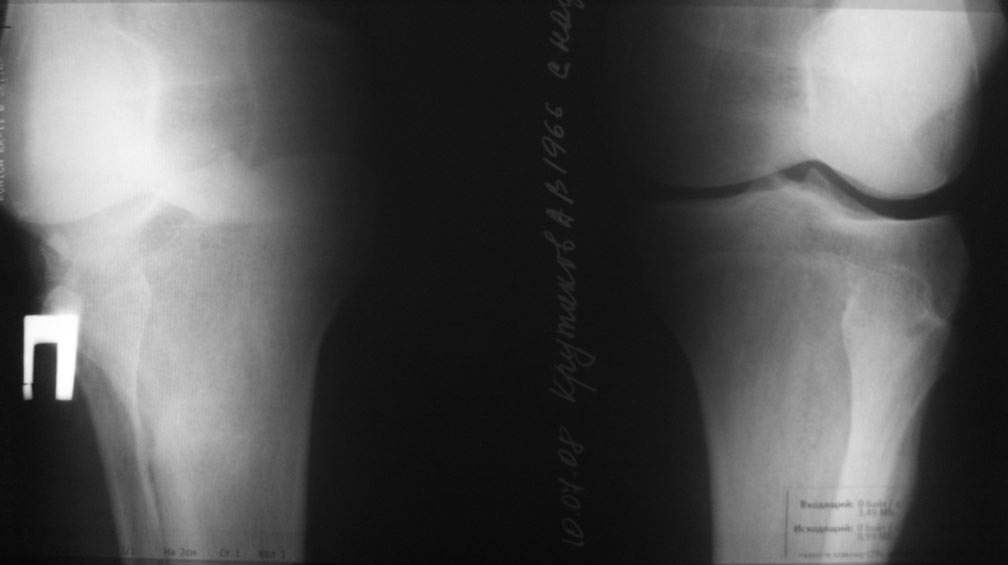

10.-Рассмотрим представленную деформацию в боковой рентгенологической проекции.

Несложные расчеты на изготовленной скиаграмме (см. рис.1 ) показывают ,что суставная поверхность проксимального отдела б/б кости, находится в положении сгибания примерно 30 гр. Плоскость деформации лежит в сагитальной плоскости. Истинный угол деформации равен примерно 15 гр., с вершиной на 4-4.5 см. (примерно) дистальнее края суставной поверхности.

Вам представленна склаграмма боковой R – гр болного вынесенного на обсуждение.

А – ось бедра.

Б – линия Blumensaat/

В – имеющаяся линия суставной поверхности б/б кости.

Г – положение суставной поверхности в норме, по отношению к продольной оси б/б кости.

Д – продольная ось голени.

86 гр. (Г-Д) отношение суставной полверхности к оси голени.

~ 30 гр. – положение сгибания.